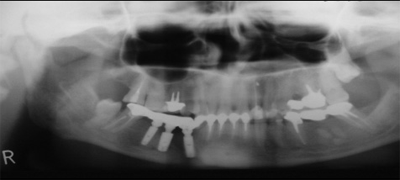

С появлением дентальной имплантации стало возможным отказаться от протезирования съемными и частично съемными протезами. В настоящее время, в предоперационном периоде, нами используется метод дентальной имплантации для замещения дефектов зубных рядов и восстановления прикуса больного, что дает возможность полного шинирования зубного ряда и получения стабильной фиксации во время хирургического вмешательства по поводу ложных суставов нижней челюсти (рис.1-5).

Рис. 3.

Применение данного метода и отказ от применения съемных и частично съемных протезов является новым функциональным и эстетическим подходом к восстановлению и получению функционально-стабильного прикуса и одним из основных этапов хирургического лечения осложнений переломов нижней челюсти, каким является ложный сустав нижней челюсти.